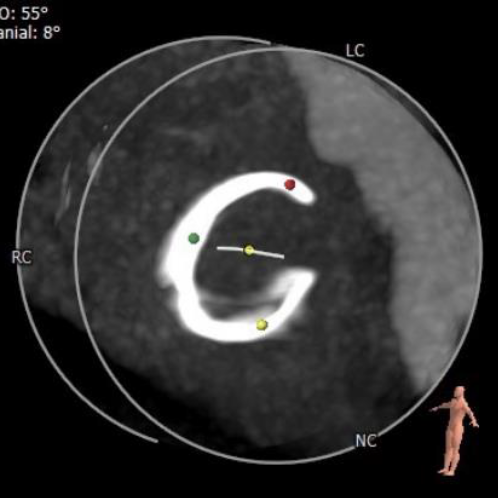

经详尽的影像学重建、评估,3D打印实物器械的模拟释放,心脏团队成员充分讨论后,决定采用经右侧颈静脉入路植入26mm规格Prizvalve®瓣膜。

CTA数据显示:患者三尖瓣位可见“C”型人工成形瓣环(28mm Edwards MC3),成形环内径22.3mm,有效开口面积381.1mm²。

借助3D打印技术模拟植入26mm Prizvalve®瓣膜,瓣膜释放后清晰显示三尖瓣成形环与介入瓣膜的形态。

使用三尖瓣成形环实物,体外模拟植入26mm Prizvalve®瓣膜,测量C型环开口尺寸(瓣周漏高发区域)。